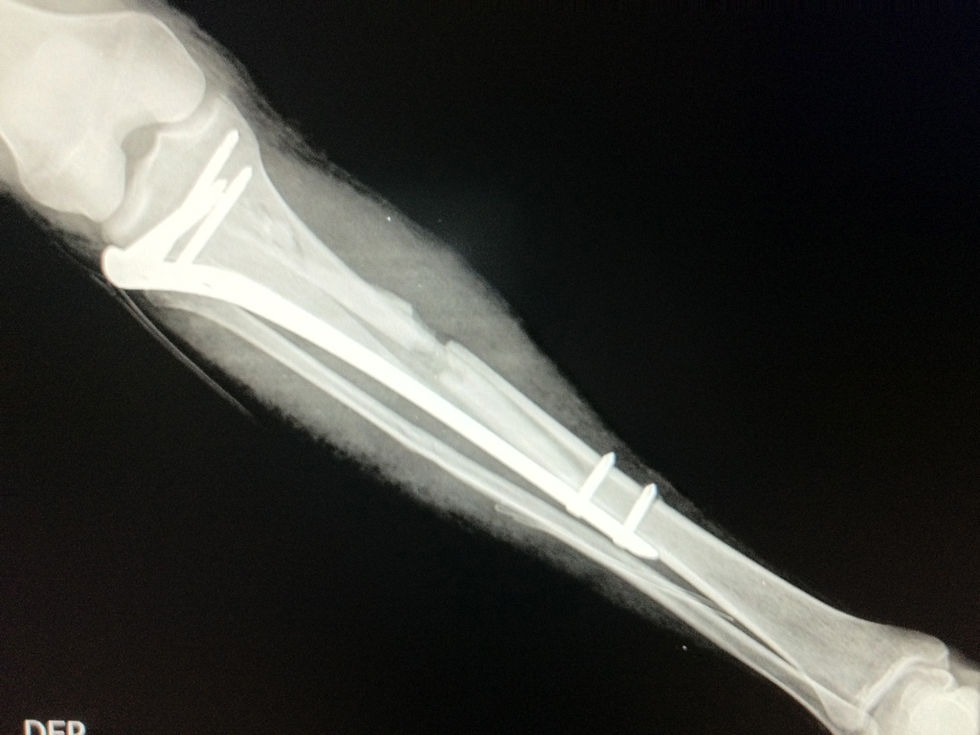

Fractura de Tibia Compleja | Osteosíntesis

La tibia es uno de los huesos del sistema musculoesquéletico que con mayor frecuencia sufre fracturas. El advenimiento de vehículos de alta velocidad, principalmente motos, asociado ocasionalmente a la ingesta de licor han resultado en un incremento en la complejidad y severidad de las fracturas en este hueso.